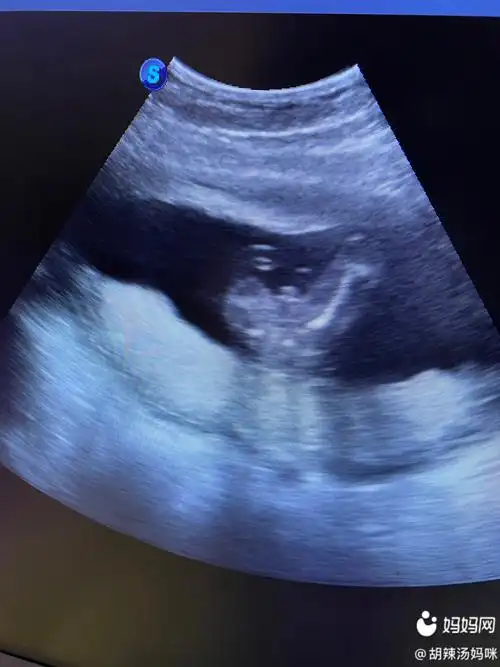

做b超检查,才18周大的小胎儿在子宫里点了个赞

孕18周胎儿特别活跃2

18周胎儿在母体内的真实图片长什么样

嘿嘿,18周,这个图有人能看出来男女吗?

胎儿18周的时候建议您到医院做一次全面的检查,通过b超您可以看到宝宝